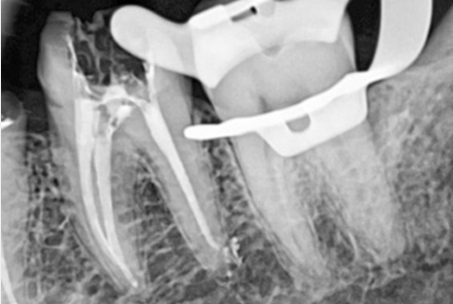

마지막으로 자연치아를 살리는 방법

치근단절제술이 불가능한 큰 어금니의 경우 치아를 발치한 후

구강 밖에서

염증의 원인이 되는 치아뿌리를 3MM 잘라낸 후

MTA라는 특수 충전재료로 뿌리 끝부분을 충전하는 술식입니다.

치아재식술은 치아뿌리가 벌어진 경우, 발치시 치아가 파절될 가능성이

매우 높기 때문에 뿌리가 벌어진 정도를 3D CT로 확인해야 합니다.

웃는얼굴치과는 3D CT를 이용하여 보다 전문적으로

치아재식술을 시행하고 있습니다.